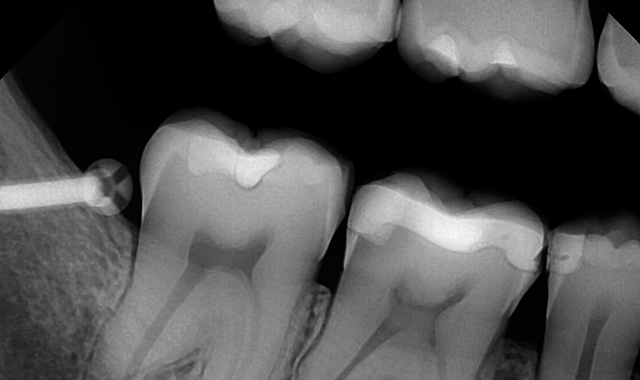

An example of a good X-ray image